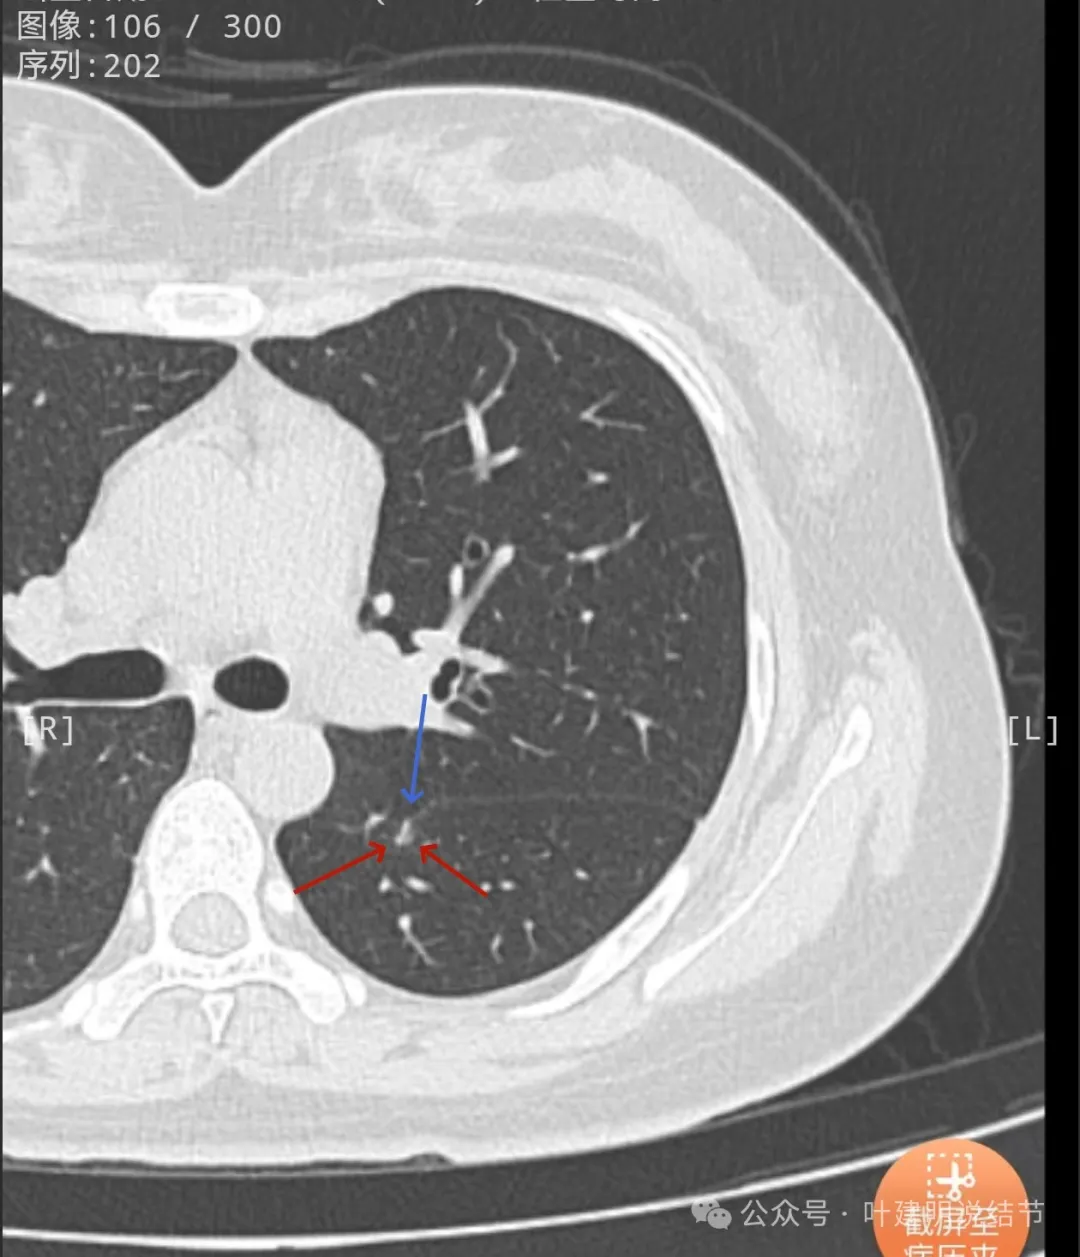

病灶现出,密度较高,贴着叶间裂。

叶间裂有牵拉,有微小血管进入病灶,灶内有小空泡征,密度整体显得较高,轮廓清楚,瘤肺边界清。